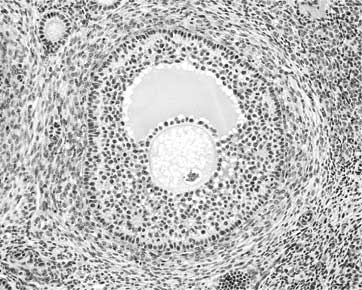

Иллюстрация к книге — Твоя жизнь до рождения: тайны эволюции человека [i_009.jpg]

Фолликул

В яичниках находятся небольшие шаровидные образования, называемые «фолликулами». В каждом фолликуле содержится одна женская половая клетка, которую называют яйцевой клеткой или сокращенно – яйцеклеткой. Яйцеклетка окружена двумя соединительнотканными оболочками и слоем клеток, обеспечивающим ей не только защиту, но и доставку питательных веществ из жидкости, заполняющей фолликул. Клеточная оболочка яйцеклетки поэтично называется «лучистым венцом», а наружная соединительнотканная оболочка, находящаяся под лучистым венцом, называется «блестящей». Блеск оболочке придают содержащиеся в ней гликопротеины – белки, имеющие в составе молекулы сахаридные остатки.

Яйцеклетка не плавает в фолликуле, а располагается не выступе, который называется «яйценосным холмиком» или «яйценосным бугорком». Фолликул содержит клетки, способные вырабатывать гормоны. Это не просто хранилище яйцеклетки, а эндокринный орган.